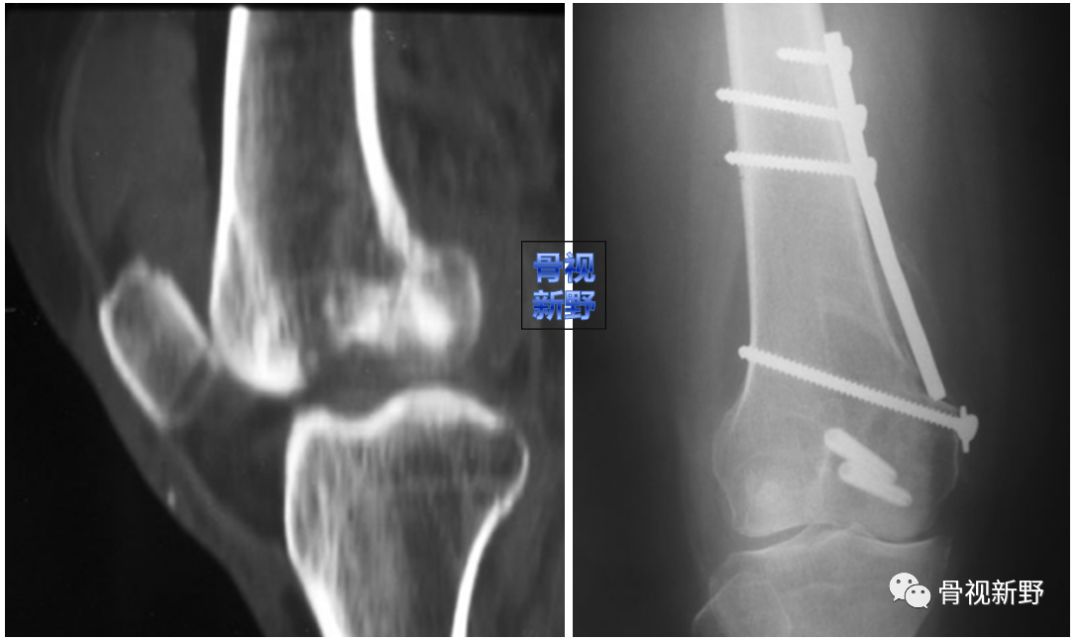

坚强内固定与关节软骨保护:坚强的固定不仅有利于解剖复位的维持,也有利于术后早期功能锻炼。采用空心拉力螺钉治疗Hoffa骨折是经典的内固定方式。AO内固定原则建议6.5mm拉力螺钉固定,尽量避开关节面。如必须穿过关节面固定,则应埋头处理。

(AO内固定原则第三版)

但因6.5mm拉力螺钉尾部大,如穿关节软骨固定,势必造成软骨面较大损伤。因此,也有人用4.5mm、3.5mm直径的拉力钉进行穿关节面固定,但得用2枚以上,且需埋头处理。

另外,对老年骨质疏松患者及髁间有压缩的患者,拉力螺钉的坚强固定可能造成骨质压缩,则会影响关节面的平整、光滑。对这类患者加用支撑钢板固定也许更合适。

Buttress理念:由于Hoffa骨折垂直剪力较大,单纯拉力钉固定易致骨折移位、畸形愈合或不愈合。

因此,使用防滑、支撑的Buttress钢板以对抗垂直剪力有一定的必要性。